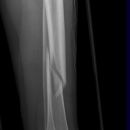

Spiralfraktur Tibia